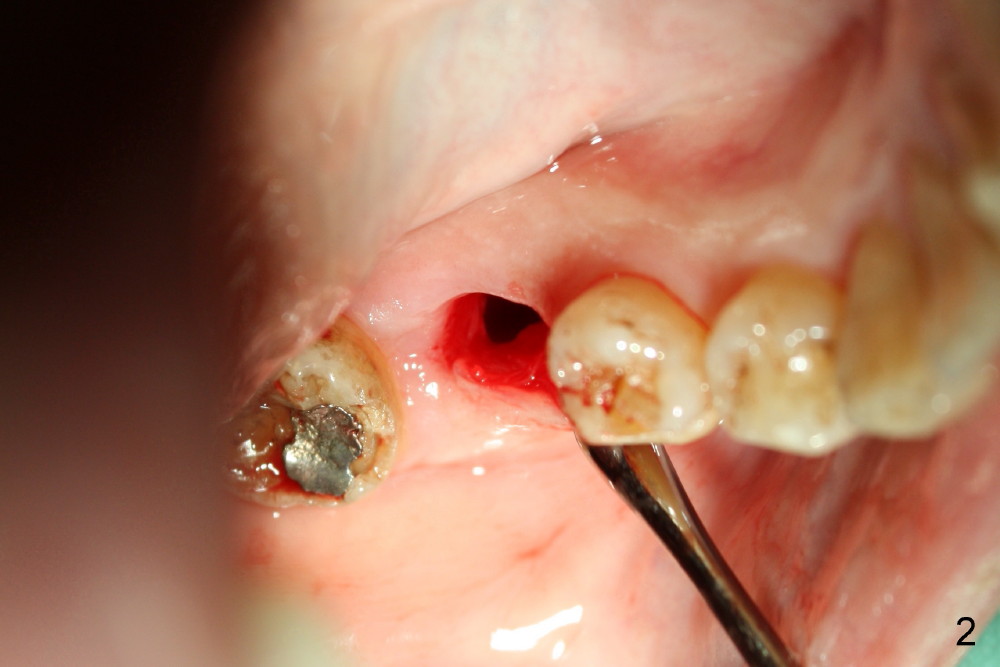

The tooth #30 was extracted in other office 1 month ago. The socket appears to heal normally. A tissue-level implant is placed as planned and smoothly. No antibiotic is prescribed pre- or post-op. The patient reports mild pain 1 week postop. There is a sign of infection. Amoxicillin is prescribed. One week later, the symptom improves, but the infection signs are present (Fig.1). The implant has mobility and is removed (Fig.2). The osteotomy is thoroughly debrided, followed by copious irrigation with normal saline and Clindamycin soaking. Irradiated cancellous bone graft (.5 mg) is placed (Fig.3,4). The wound is covered by collagen plug (Fig.5) and sutured with Chromic gut (Fig.6). Amoxicilin is prescribed postop. One week follow up reveals normal wound healing (Fig.7 (buccal view), 8 (lingual)).